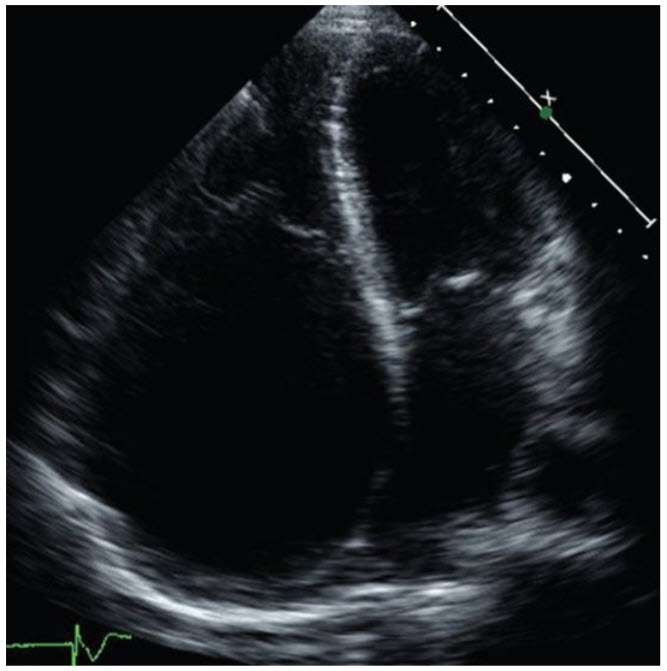

A 26-year-old woman presents to your office for evaluation. She was told she had a murmur many years ago. She has a history of palpitations, but is otherwise asymptomatic. On examination, she is in no acute distress. Prominent v waves are noted in the JVP. Carotid upstrokes are normal. Chest is clear to auscultation. Cardiac examination reveals a nondisplaced PMI. Auscultation reveals a widely split first heart sound, with a loud second component that sounds like a click. A holosystolic murmur is heard at the right sternal border, which increases with inspiration. Hepatomegaly is present. An echocardiogram is performed (Fig. below).